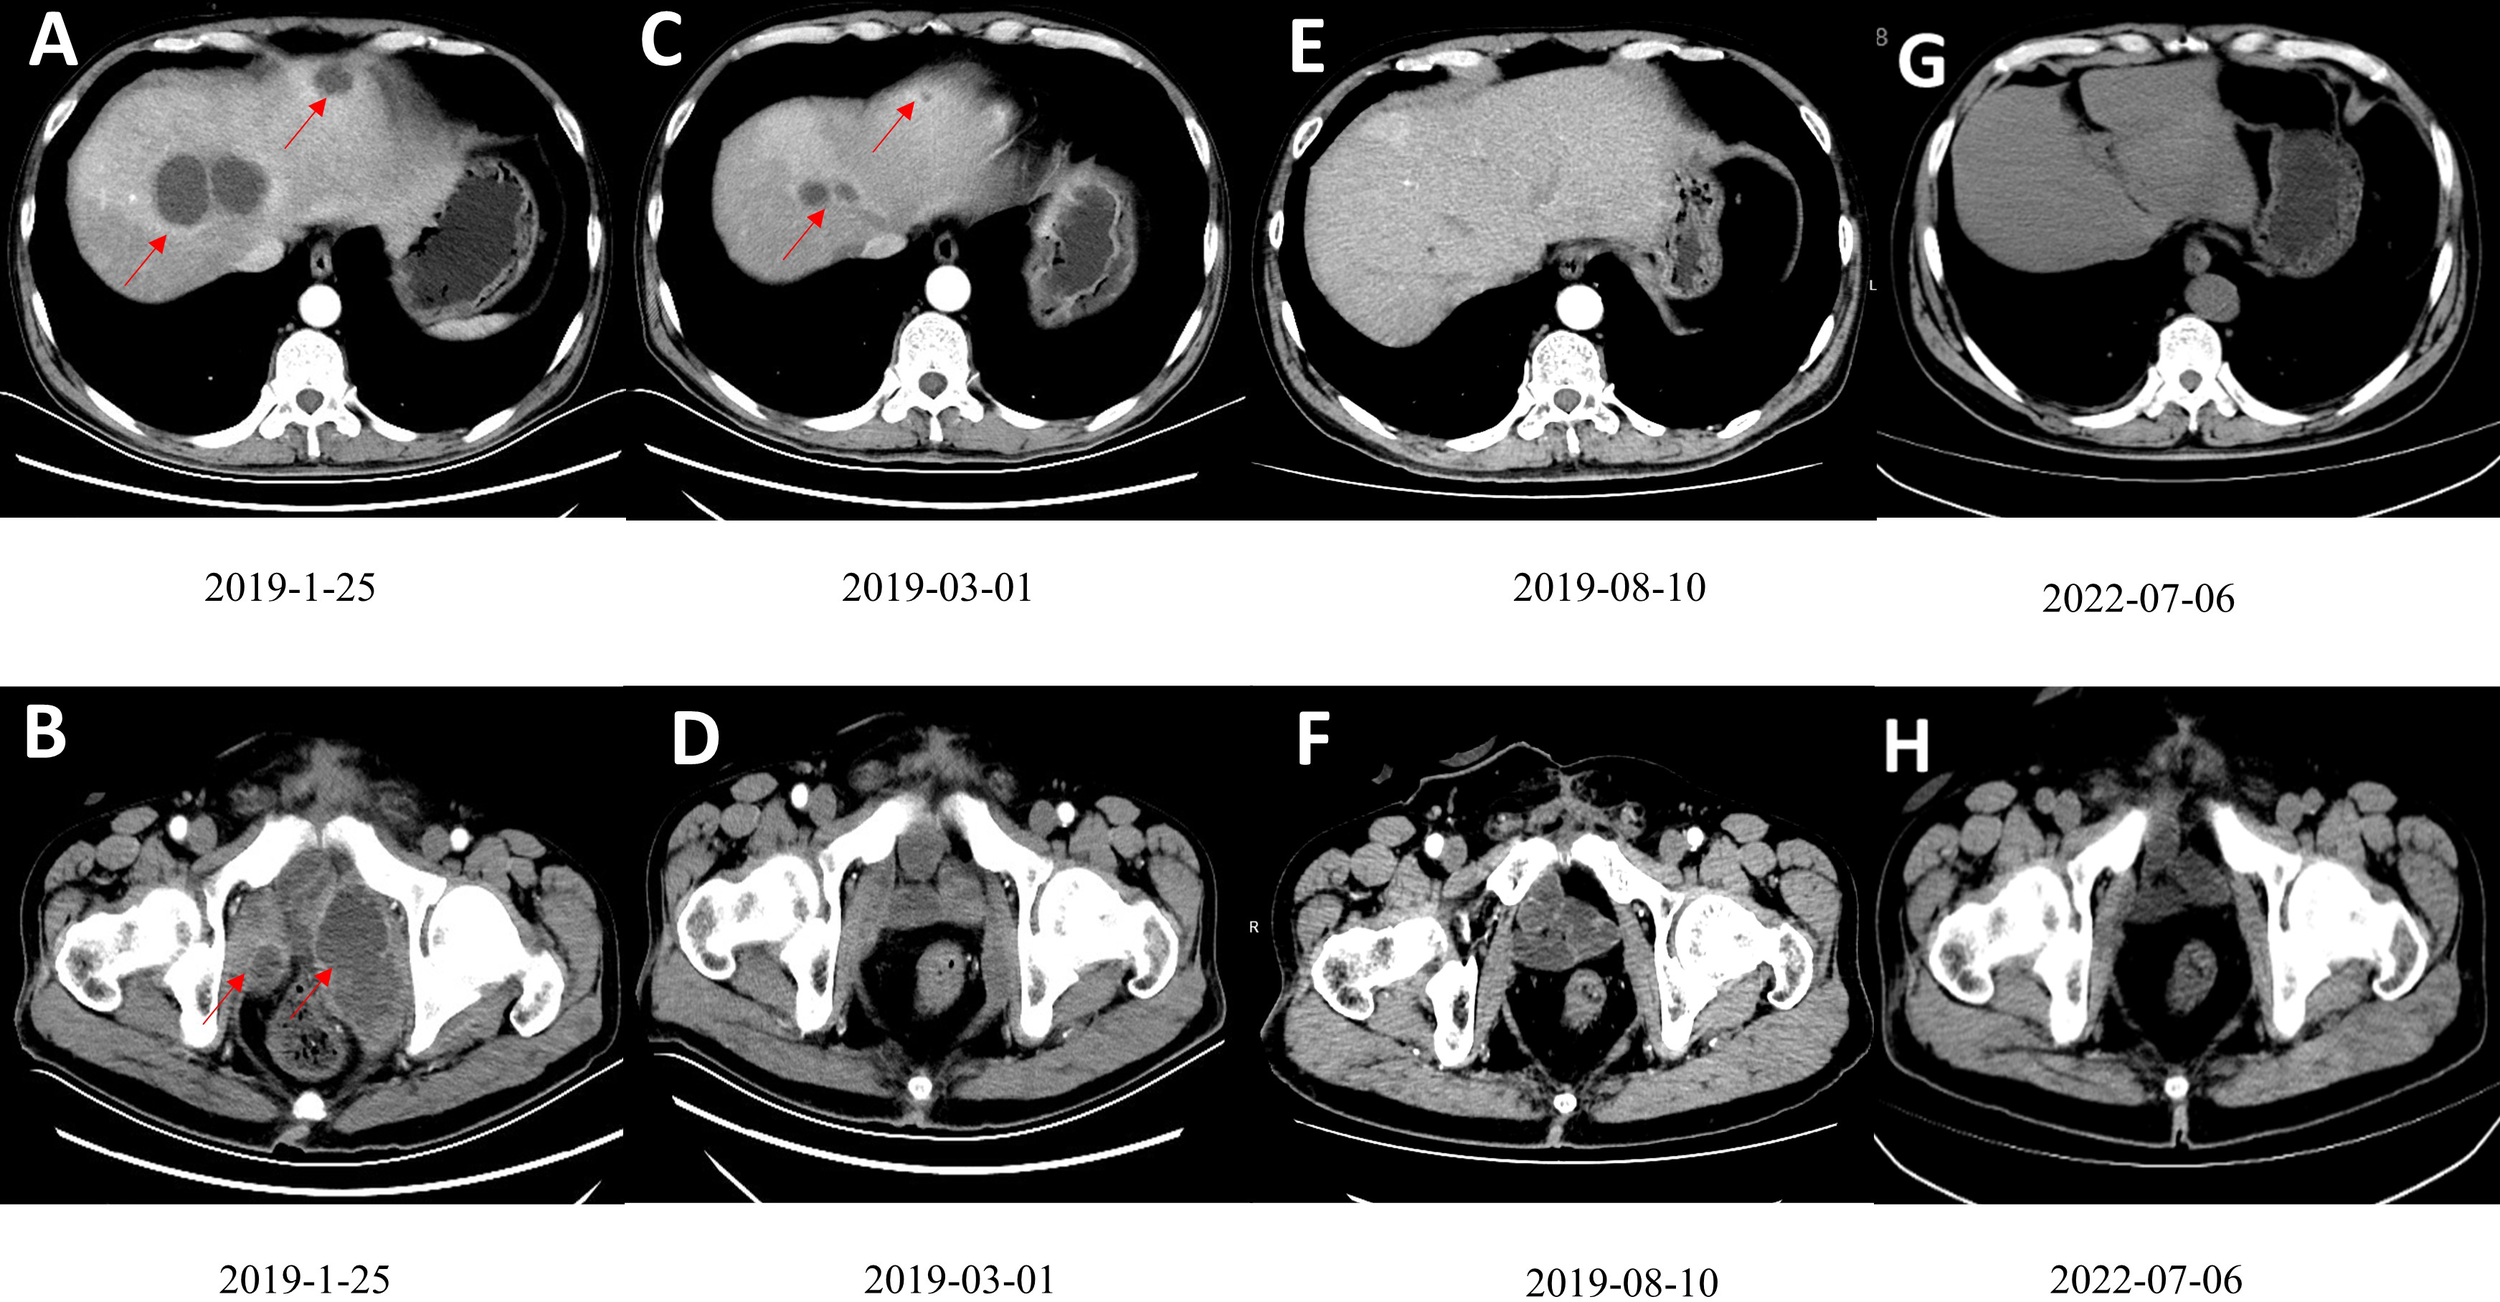

In December 2018, the abdominal enhanced CT and positron emission computed tomography image (PET-CT) showed multiple pelvic metastases. The patient was then transferred to our hospital. In January 2019, the abdomen enhanced CT showed multiple metastases in liver and pelvic cavity (Figures 1A, B). After carefully informed and with the patient’s content, the patient started the treatment of anti-PD-1 antibody in combination with Nab-paclitaxel in January 2019. As sintilimab was the only anti-PD-1 antibody available in our hospital at that time, the patient was treated with sintilimab (200mg ivgtt q3w) in combination with Nab-paclitaxel (100mg ivgtt qw) in January 2019. The patient was examined during therapy for routine blood, thyroid, liver, and kidney function, as well as coagulation and serum tumor markers. Following three cycles of treatment, the patient had abdomen CT examination to determine the treatment's efficacy. The evaluation criteria were based on the solid tumor efficacy evaluation criteria (RECIST).

Figure 1

(A, B) Contrast-enhanced CT scan showed multiple low-density tumors of various sizes in the pelvis and liver, and the largest liver metastatic tumor was 4.6cm×3.9cm. (C, D) A contrast-enhanced CT scan after three courses of treatment showed that the tumors in the pelvis and liver had shrunk significantly. (E, F) After ten cycles of treatment, CR was observed. (G, H). The patient had been disease free for 41 months. Figures G and F are the most recent follow-up results.

On March 1, 2019, after the patient had finished 3 cycles of combined therapy, the whole abdomen enhanced CT showed that liver and pelvic metastases were reduced significantly (Figures 1C, D). On July 21, 2019, nab-paclitaxel was discontinued (8 cycles, 24 chemotherapy doses in total) while sintilimab maintenance monotherapy (200 mg q3w) was continued. On August 10, 2019, after 9 cycles, the patient achieved CR (Figures 1E, F). Sintilimab monotherapy (200 mg q3w) was administered for 2 years (32 immunotherapy doses in total) and stopped in January 2021. The patient developed fatigue and mild rash during the treatment, with no serious adverse reactions. The disease has been kept CR for more than 41 months and is still being followed up without recurrence and adverse events (Figures 1G, H). The patient’s imaging before and after nab-paclitaxel combined with sintilimab treatment are also presented as Supplemental Materials (Supplemental Videos 1, 2).